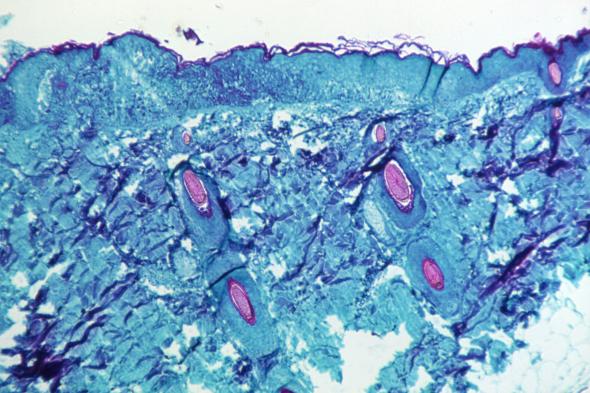

Tejido infectado con la viruela del monoSmith Collection/Gado via Getty Images

Investigadores del Instituto de Salud Carlos III de España han conseguido el primer borrador de la secuencia completa del virus causante de la viruela del mono (Monkey Pox) a partir de las muestras de 23 pacientes.

La secuenciación completa ha confirmado que el virus de la viruela del mono del brote que se está produciendo en España y otros países pertenece a un grupo fitogenético de África Occidental, que es el de menor virulencia entre los conocidos y el que se ha identificado por el momento en la mayoría de los países fuera de África implicados en este brote.